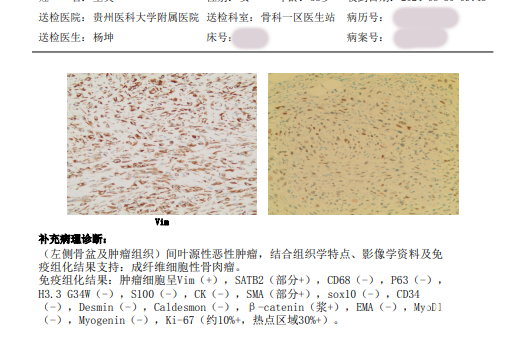

患者术前检查单

患者术前检查单

据了解,患者王兰(化名),53岁,因左髋部进行性疼痛不适持续四月余,并伴有体重减轻3公斤的症状,前往当地医院就诊。经过初步检查,医生怀疑其为左侧骨盆肿瘤,并建议转至上级医院进行进一步治疗。2024年7月,患者辗转多家医院后,最终来到贵州医科大学附属医院骨肿瘤门诊就诊。经过穿刺病理检查,确诊为“骨盆恶性肿瘤骨肉瘤”。